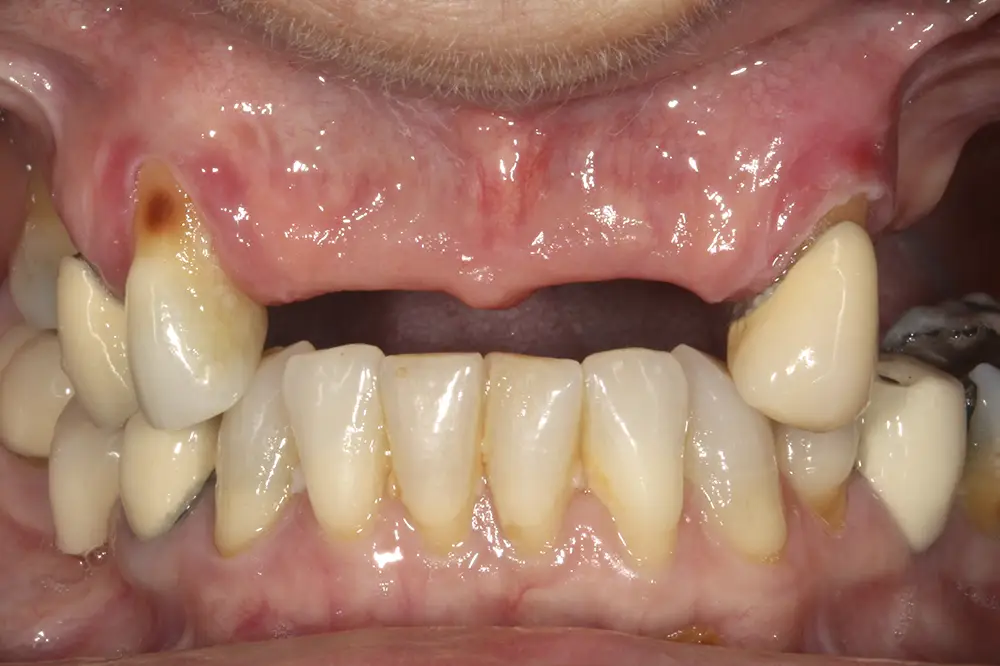

Al retirar las prótesis en las imágenes laterales, observamos además un colapso de la zona anterior y recesiones en todas las piezas que aún conserva la paciente (figs. 5 y 6). En la radiografía inicial observamos pérdidas óseas elevadas en el molar del primer cuadrante y el premolar de este mismo sector, por lo que se decide su exodoncia y regeneración con PRGF, que se realizará el mismo día de la primera fase de inserción de los implantes. En el arco inferior hay también problemas con los sectores posteriores, con pérdidas óseas en el cuarto cuadrante y signos de fractura vertical en el puente 44-46 y caries radicular en las piezas 35 y 36 (fig. 7). Por ello, estas piezas inferiores son también candidatas a la exodoncia, regeneración y reposición con implantes dentales, para lograr una posterior rehabilitación funcional.

Figs. 5 y 6. Imágenes laterales de la paciente sin su prótesis. Al retirarla, se hace evidente el colapso de la dimensión vertical y la pérdida ósea y recesión de los dientes pilares que sostienen la prótesis removible.